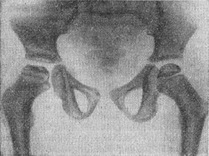

![]() Рис. 1. Хвороба Пертеса, II стадія. Сплощення епіфіза лівої стегнової кістки, ущільнення його структури, розширення смужки метаэпифизарного хряща і розширення рентгенівської щілини лівого кульшового суглоба. |

II. Стадія імпрессіон перелому епіфіза стегнової кістки. Рентгенологічними ознаками хвороби в цій стадії, що триває 6-8 міс., є сплощення епіфіза стегнової кістки, ущільнення його структури і розширення рентгенівської суглобової щілини. Смужка метаэпифизарного хряща набуває деяку звивистість, що вказує на порушення енхондрального росту кістки. Ці ознаки протягом зазначеного строку поступово наростають (рис. 1).